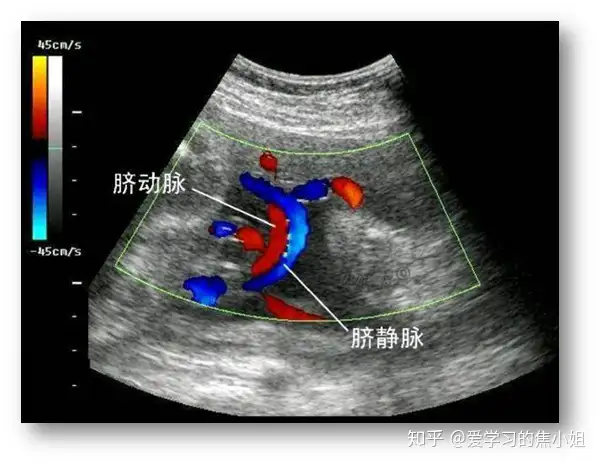

十、单脐动脉

单脐动脉(SUA):在胎儿脐索内及膀胱周围仅有一条脐动脉,另一条脐动脉缺如。单纯单脐动脉与胎儿单倍体畸形无关,与胎儿非染色体异常的关系: 与胎儿肾脏发育不良、心脏畸形和低体重儿有关。发现胎儿有单脐动脉时,应仔细检查其他解剖结构,超声评估并随访观察胎儿生长发育情况。合并畸形或见染色体异常软指标,应做胎儿染色体检查。

SUA可以单发,合并染色体异常及其他畸形也不少见,约50%的18三体和 10%-50%13三体儿伴有SUA。最近有报道SUA发生心脏畸形、肾脏畸形和IUGR(宫内生长受限)的风险明显增加。